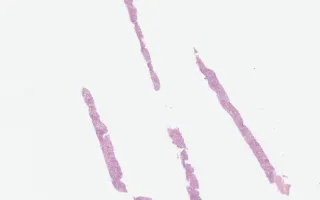

Liver, Alcoholic liver disease, H&E stain

The H&E findings in this biopsy are of a steatohepatitic process characterized by severe steatosis, many ballooned hepatocytes and Mallory hyaline (intracytoplasmic inclusions composed of cytokeratins and ubiquitin). A prominent ductular reaction and mild cholestasis is also seen.

The above findings are also seen in the context of non-alcoholic fatty liver disease (NAFLD). While distinguishing NAFLD and ALD may often be difficult or impossible, the prominence of Mallory hyaline, the degree of ductular reaction and central hyaline sclerosis seen in this biopsy are suggestive of alcoholic liver disease.

This slide shows H&E stain. See Related Content for Trichrome stain.